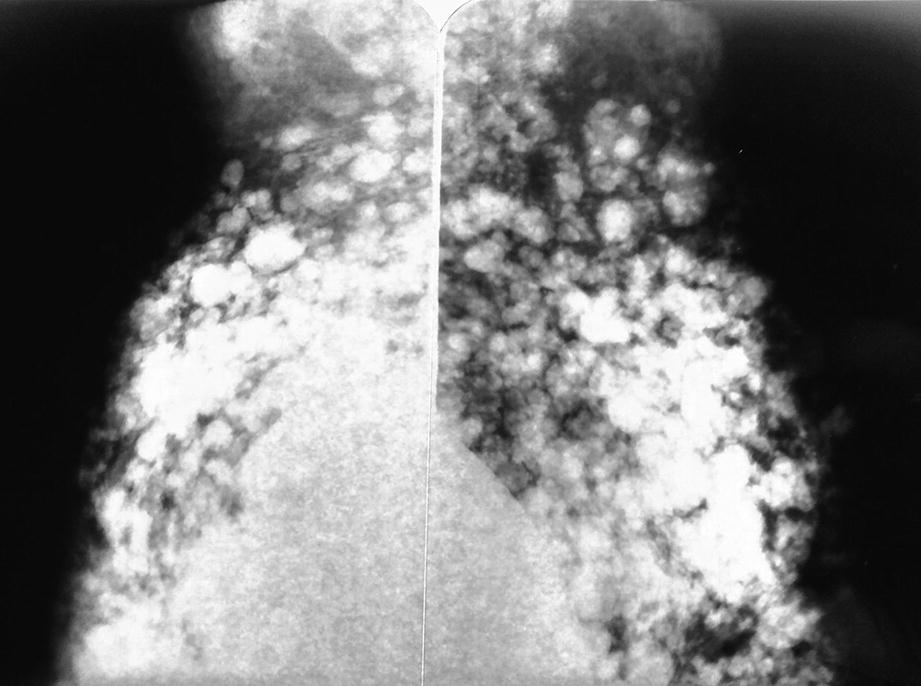

Silicones in the axilla. Mammography showing silicone in the axilla. Bilateral mammography is observed in an oblique view, in breasts with prosthetic implants from which there is abundant silicone that not only spread through the breast but also migrated to the axilla

Silicone in the axilla. Mammography showing more detail of the axillary region. Note that a large part of the axilla is filled with silicone

Silicone in the axilla. The lower axillary region is already affected by the migration of silicone

Silicone in the axilla. Mammogram where opacities are seen as a result of the past injection of silicone